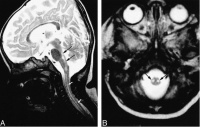

言语不清,嗜睡2天,于2005年11月24日急诊入院。2005年11月20日上午,患者在广州某镇探亲时家务劳动后,上楼时出现行走无力,下午自觉视物模糊,不伴发热、恶寒、头痛、头晕、咳嗽、咽痛、恶心、呕吐等症状。11月21日上午患者步行到广州市某镇医院按“上呼吸道感染”治疗无效。11月22日下午患者出现行走无力加重,需人搀扶,并出现言语欠清晰、精神差,被家人于当晚送回湖南当地县人民医院诊治。查体:嗜睡,反应迟钝,言语欠清晰,口角向左歪,伸舌右偏,右上下肢肌力IV级,左上下肢肌力正常,病理反射(—)。头颅CT平扫未见异常。按“脑梗塞”治疗病情无好转,故于11月24日下午转至我院神经内科重症监护病房按重症脑梗塞诊治。入院时查体:T36.7℃P86次/分R20次/分BP105/71mmHg嗜睡,言语欠清晰,右眼睑稍下垂,右眼内收及左眼外展受限,右侧鼻唇沟稍变浅,伸舌右偏,双侧咽反射减弱,心、肺、腹均未见异常,左上、下肢肌力IV级加,右上、下肢肌力III级加,四肢肌张力稍低,腱反射减退,指鼻及轮替试验及感觉功能检查无法配合。颈软,克、布氏征(—),右巴氏征(+),左巴氏征(—)。实验室检查:血常规:WBC总数:10.4×109/L,分类正常;电解质、肝、肾功能血脂血糖血气分析均正常。11月25日上午患者出现昏睡,完全性失语,四肢肌力明显减退,右上肢肌力0级,左上、下肢及右下肢肌力均II级。查头颅MRI示:中脑与桥脑交界处见片状稍长T1稍长T2信号,边界欠清晰,中脑导水管及第四脑室未见明显受压;头颅MRI增强:脑干异常信号,未见明显强化,考虑脑干梗塞。11月26日患者陷入浅昏迷,腰穿查脑脊液压力95mmH2O,外观无色,清亮,潘氏实验(+),总蛋白定量0.58g/L,白细胞数76×106/L,单个核细胞90%,多个核细胞10%,葡萄糖2.59mmol/L,氯化物117mmol/L,故诊断为脑干脑炎,给予地塞米松10mg静滴,每日一次,同时予抗病毒,抗感染等治疗,12月2日患者意识转清醒,但言语模糊不清,右上肢肌力II级,右下肢肌力0级,左上下肢肌力II-III级。14天后停地塞米松改为口服强的松30mg/天,逐渐减量,患者入院第20天因经济困难出院,出院时查体:右眼内收及左眼外展受限,伸舌稍右偏,双上肢肌力III-IV,双下肢肌

脑干脑炎

力III级,病理征阴性,复查脑脊液:压力180mmH2O,无色,清亮,潘氏实验(—),脑脊液蛋白定量0.23g/L,白细胞数16个/L,单核细胞为主,葡萄糖3.4mmol/L,氯化物128mmol/L。2006年1月17日复诊:患者仍行走不稳,需人搀扶。查:神清语利,计忆力、定向力、记算力正常,双眼球运动正常,双鼻唇沟对称,伸舌稍右偏,四肢肌力肌张力正常,双巴氏征阳性,深浅感觉检查正常。双侧指鼻试验稍差,Romberg征睁眼(+),闭眼(+)。脑电图正常;视觉、脑干听觉诱发电位检查:右眼VEP潜伏期延长,波幅在正常范围内;左眼VEP潜伏期、波幅在正常范围内;右耳BAEP波形分化不良,左耳BAEPⅠ、Ⅲ、Ⅴ波幅,潜伏期正常;四肢肌电图检查:左腓总神经运动传导波幅降低。2006年3月15日随访,患者行走正常,完全康复。查体无异常。

讨论:脑干脑炎临床表现多种多样,但缺乏典型的症状和体征,容易误诊。本病例患者以突发肢体瘫痪起病,发病前无感染史及病程中无发热史,头颅CT平扫未见异常,头颅

MRI增强:脑干异常信号,未见明显强化,考虑脑干梗塞。故临床误诊为重症脑梗塞。误诊原因可能为:(1)近年来青壮年脑梗塞发病率增高;(2)临床医生对突发肢体瘫痪和意识障碍患者,过分依赖头颅CT和MRI等影像学诊断结果;(2)发病前无感染史及发病前后病程中无发热史导致忽视了炎性疾病的可能。文献报道脑干脑炎的发病特点为:1.任何年龄都可发病,以青壮年居多。2.大多患者发病前1—4周有上呼吸道感染或其他病毒感染史。3.起病急骤,往往早期出现精神症状和意识障碍,通常在较短时间内出现双侧脑神经麻痹,伴有一侧或双侧的肢体运动障碍感觉障碍,但长束征少见,症状和体征较弥散很少局限于某一部位,4.脑脊液基本正常,蛋白轻度增高,细胞以淋巴细胞和单核细胞为主。5.病程常有自限性,经7—8周治疗后大部分好转或痊愈。6.激素早期治疗有效,预后好。7.头颅CT和MRI的异常率低。本例开始按脑梗塞治疗效果不佳,发现脑脊液异常后,按脑干脑炎以地塞米松等治疗,患者完全康复。我们推测该病发病机制可能是病毒的直接侵润损伤或病毒感染后的免疫损伤。MasaakiOdaka等研究认为许多Bickerstaff脑干脑炎患者都合并有Guillain-Barre综合征轴突改变,暗示这两种病是相近的,二者属于同一疾病谱。